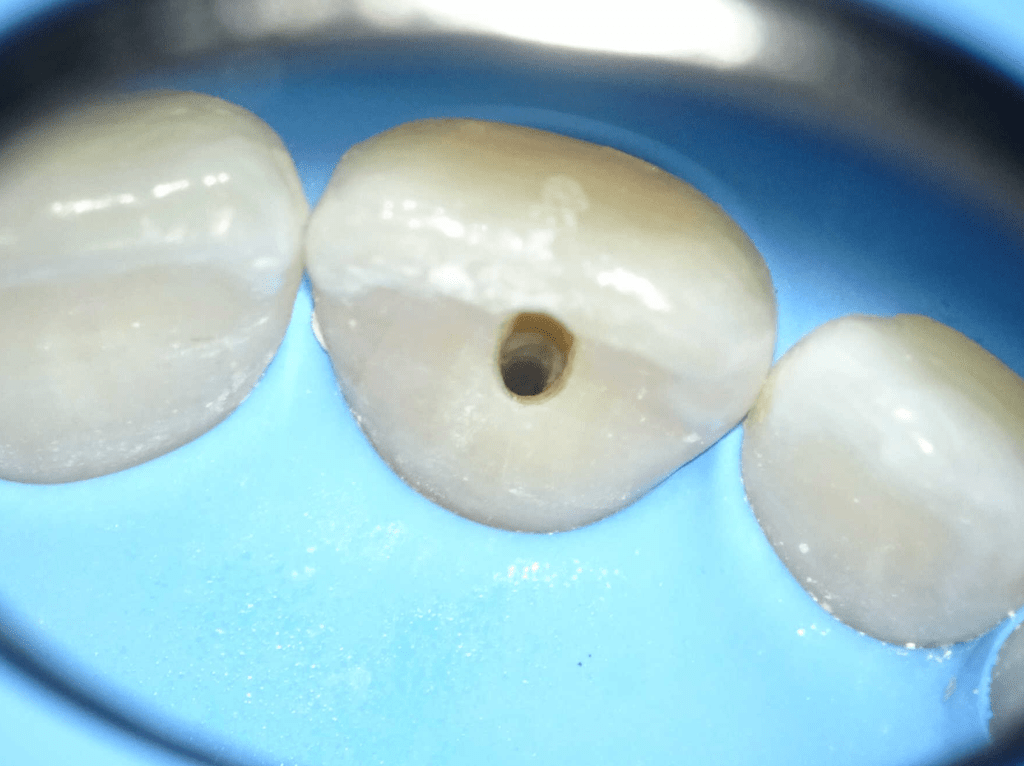

Acceso ultraconservador a través de incrustación reciente